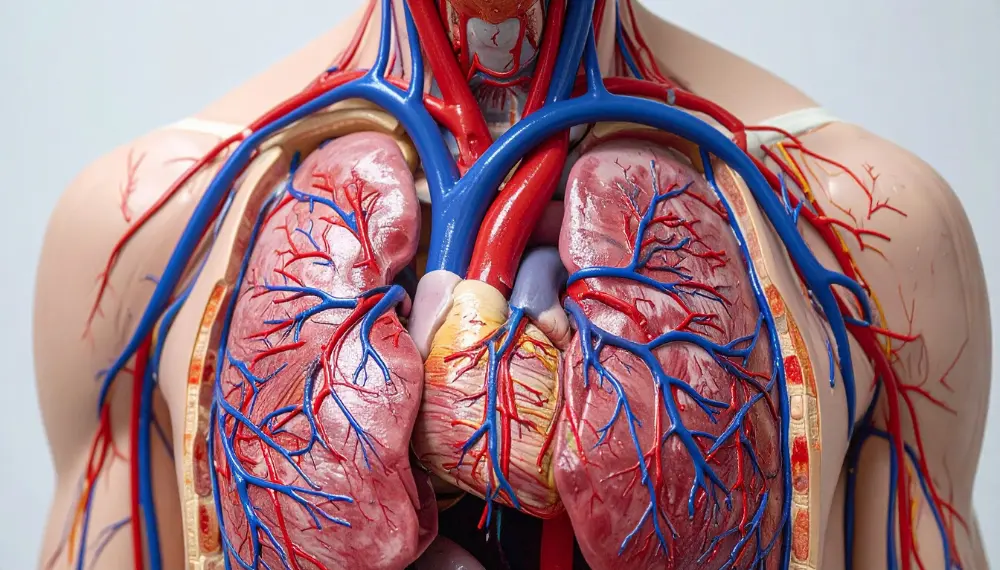

توسعه مویرگی به افزایش تعداد، چگالی و شبکه ارتباطی مویرگها در تارهای عضلانی گفته میشود. مویرگها کوچکترین رگهای خونی بدن هستند که وظیفه اصلی آنها تبادل اکسیژن، مواد مغذی و مواد دفعی میان خون و سلولها است. وقتی که فرد فعالیت ورزشی منظم دارد، بدن بهتدریج به شرایط جدید سازگار میشود. این سازگاری یکی از مهمترین عوامل پیشرفت عملکرد ورزشی است. یکی از اصلیترین سازگاریهای فیزیولوژیکی، همین توسعه مویرگی میباشد.

در فرآیند مویرگ زدن در ورزش، عضلاتی که تحت فشار تمرینی قرار گرفتهاند، بهمرور نیاز بیشتری به اکسیژن و حذف مواد زائد مانند اسید لاکتیک پیدا میکنند. در نتیجه بدن از طریق مکانیسمهای بیولوژیکی از جمله تحریک فاکتورهای رشد عروقی (مانند VEGF)، شروع به ساخت مویرگهای جدید کرده یا قطر و کارایی مویرگهای موجود را افزایش میدهد. این تغییر موجب میشود تبادل اکسیژن و مواد مغذی سریعتر و کارآمدتر انجام شود و در نتیجه توان و استقامت ورزشکار به شکل قابلتوجهی افزایش یابد.

از نظر پزشکی نیز توسعه مویرگی نقش مهمی در سلامت عمومی بدن ایفا میکند. با افزایش تعداد مویرگها، خونرسانی بهتر شده و خطر بروز بیماریهای قلبی–عروقی کاهش مییابد. علاوه بر این، افراد با شبکه مویرگی قویتر معمولاً سطح انرژی بالاتری دارند، متابولیسم آنها کارآمدتر است و قابلیت ریکاوری عضلانی آنها پس از تمرینات شدید افزایش مییابد.

از طرفی، تمرینات هوازی، حجم ضربهای قلب را افزایش داده و جریان خون بیشتری را به عضلات منتقل میکنند. افزایش جریان خون یکی دیگر از عوامل تحریککننده فرآیند توسعه مویرگی است. در این مسیر، آنزیمهای اکسیداتیو نیز در عضلات افزایش مییابند. این آنزیمها به بهبود سوختوساز چربی و کربوهیدرات کمک کرده و از تجمع مواد مضر جلوگیری میکنند.